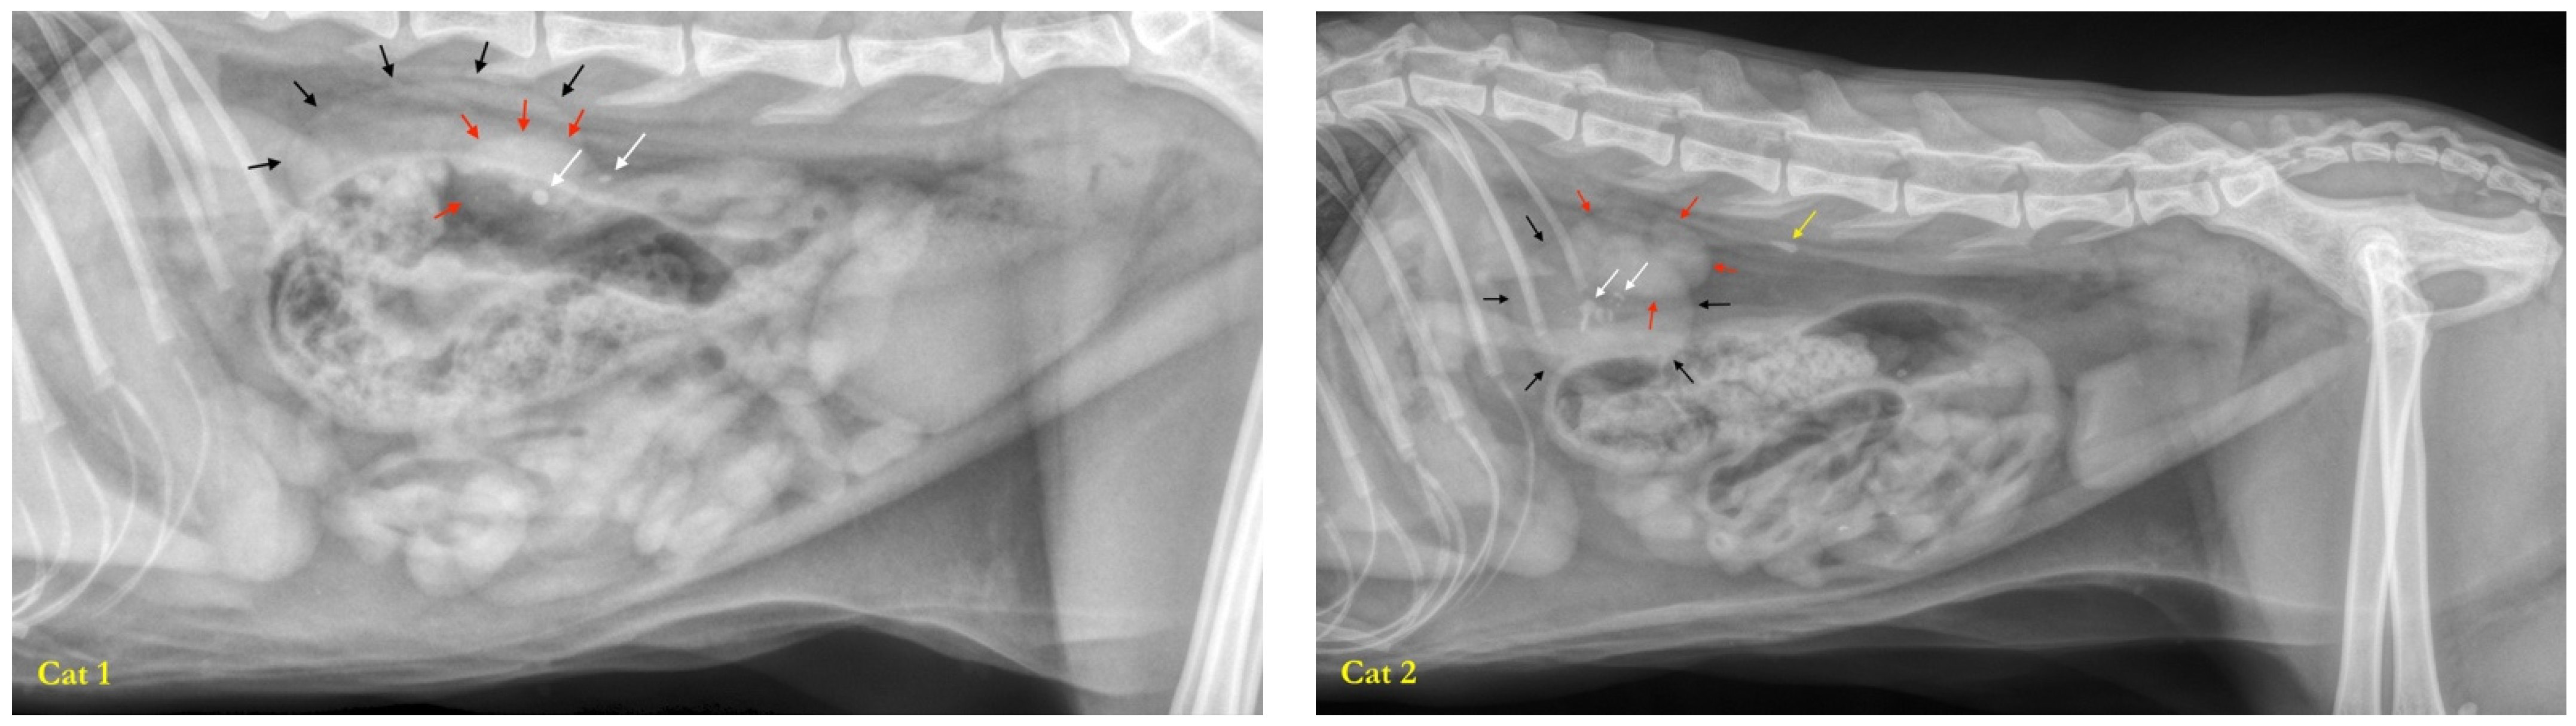

2.1. Studied Population

2.1.1. Recruitment of Cats

2.1.3. Health Status

2.1.4. Inclusion Criteria

2.1.5. Exclusion Criteria

3.1. Studied Population